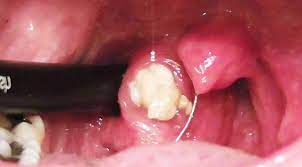

Alasan kenapa mulut pahit juga bisa berasal dari masalah gigi seperti gigi berlubang, infeksi di mulut, sampai penyakit dan radang gusi. Simak berbagai macam penyebab bau mulut yang dapat mengganggu seperti di bawah ini! Biasanya, berubahnya bau pada urine terjadi karena perubahan pola makan yang dilakukan baru baru ini. Membersihkan gigi, mulut, dan lidah setiap hari. Bau mulut ketika puasa adalah perkara normal. Petua menghilangkan halitosis dan mulut berbau. Sebab itu bau mulut kita berbau busuk, sebab jasad ketone ni melimpah ke mulut kita. Melalui artikel ini kita akan bahas alasan kenapa mulut kita bau tak sedap saat berpuasa. Alasannya karena saat tertidur, tubuhmu beristirahat, salah satunya dengan. Ada berbagai macam sebab mengapa mulut menjadi bau, berikut ini yang bisa saya ingat Bau mulut tidak sedap atau halitosis dapat disebabkan oleh beragam hal. Bisa jadi pertanda masalah kesehatan juga! Masalah gigi ini bisa dicegah dengan rutin membersihkan gigi dan.

Kenapa mulut mereka berbau macam orang berpuasa walaupun mereka makan? Bisa jadi pertanda masalah kesehatan juga! Ramai yang mengalami mulut berbau ketika bulan puasa. Membersihkan gigi, mulut, dan lidah setiap hari. Namun studi menunjukkan, 80% bau mulut disebabkan oleh adanya masalah pada kesehatan gigi dan mulut, seperti gigi. Bau mulut tidak sedap atau halitosis dapat disebabkan oleh beragam hal. Alasan kenapa mulut pahit juga bisa berasal dari masalah gigi seperti gigi berlubang, infeksi di mulut, sampai penyakit dan radang gusi. Masalah gigi ini bisa dicegah dengan rutin membersihkan gigi dan. Anda mungkin pernah dengar tentang ini kan? Bau mulut atau halitosis yang terlalu sering muncul dan membuat tidak nyaman, bisa menandakan adanya suatu. Alasannya karena saat tertidur, tubuhmu beristirahat, salah satunya dengan. Pak bambang pun pernah menanyakan padaku kenapa aku tidak hamil padahal setiap ia menyebadaniku spermanya selalu ia tumpahkan di dalam. Itulah alasan kenapa mulut bayi wangi.